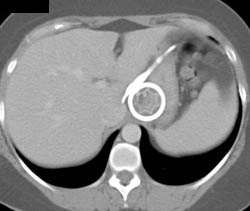

Gastric Polyps in Familial Polyposis With Desmoid Tumor